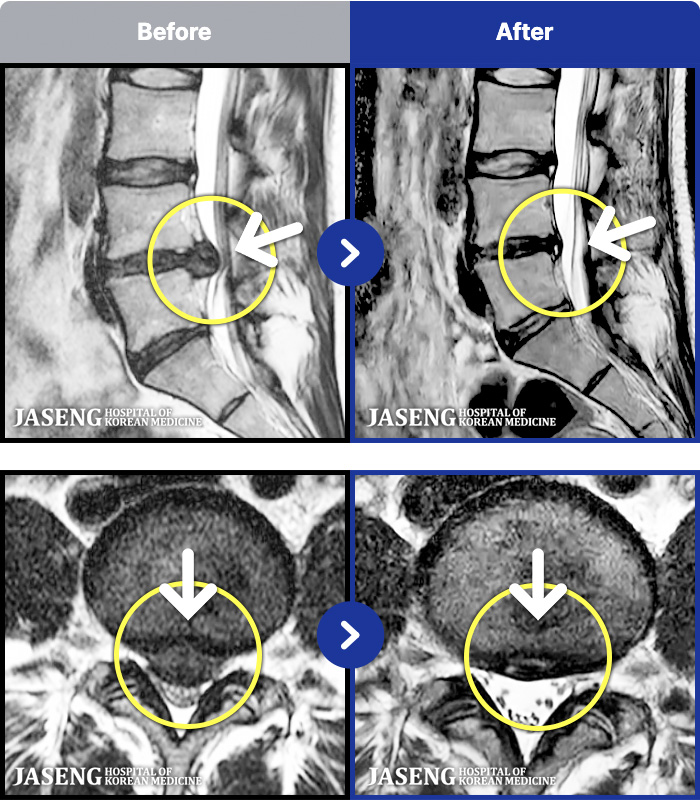

MRI ġ

1,245 MRI ũ ʸ Ȯϼ.